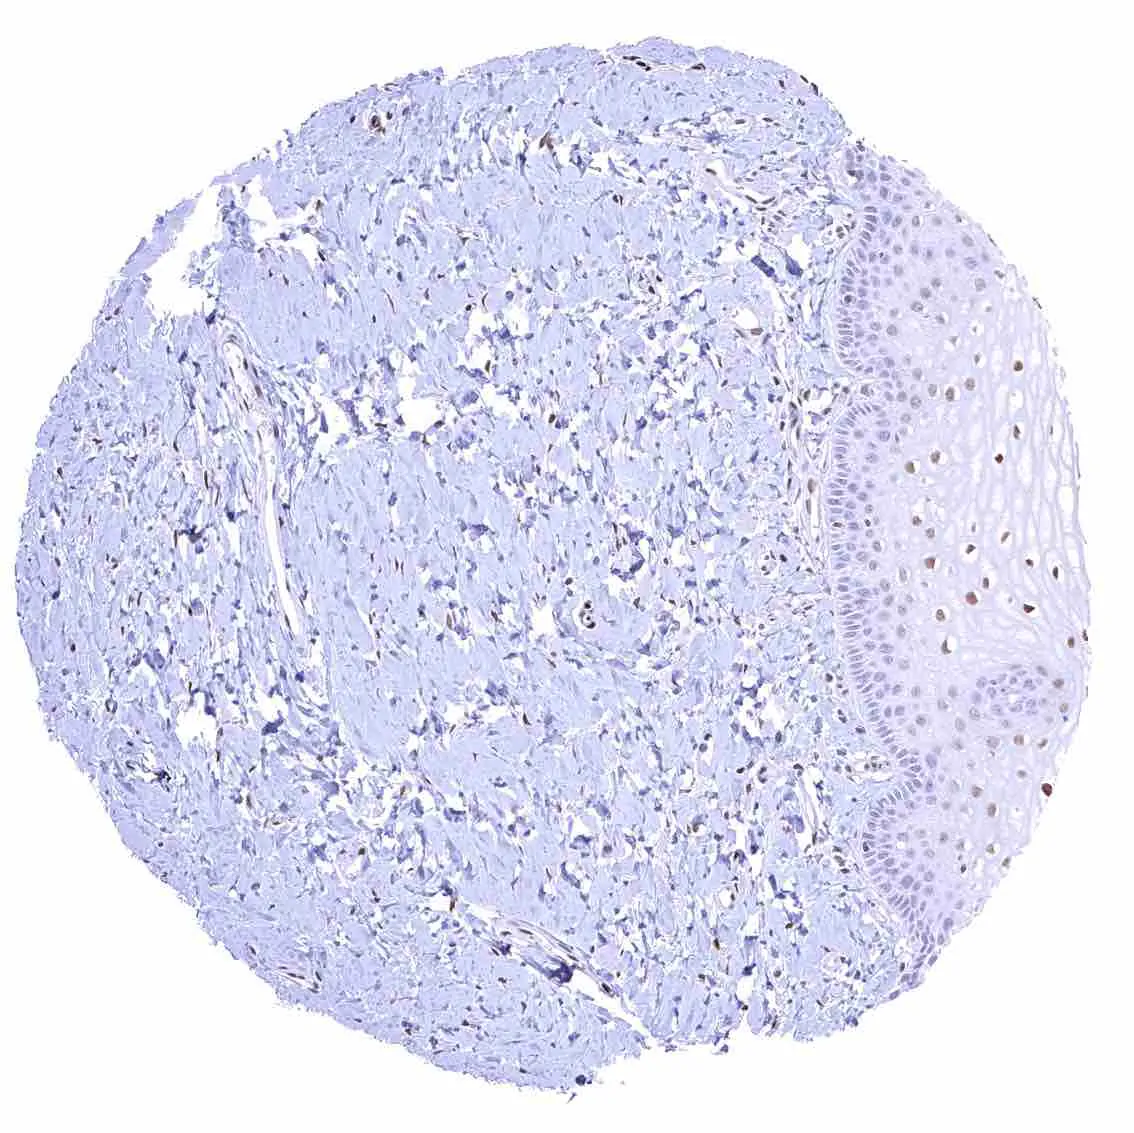

p27 Kip1 antibody [HMV3970] HistoMAX™

Appendix, mucosa – Among epithelial cells, nuclear p27 staining predominates in superficial epithelial cells. Most p27 staining occurs in lymphatic cells, however.

Appendix, muscular wall – Nuclear p27 staining of variable intensity in a fraction of smooth muscle and of neuronal cells.